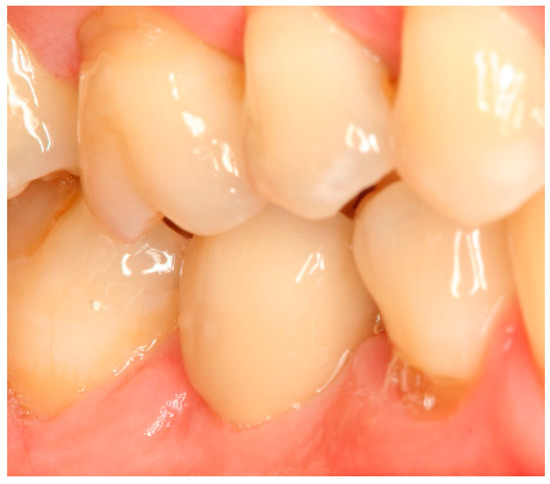

Situation after crown cementation. Lateral view.

Figure A2.

Clinical situation at the 1-year follow-up. Lateral view.

Figure A5.

Clinical situation at the 3-year follow-up. Lateral view.

Figure A8.

Clinical situation at the 5-year follow-up. Lateral view.

Figure A11.